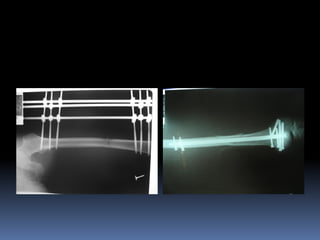

 Tại SaoTôi Phải Cố Định Xương Gãy? Bằng Cách Nào?

 Tại SaoTôi Phải Cố Định Xương Gãy? Bằng

Cách Nào?

 Tại SaoTôiPhải Cố Định Xương Gãy? Bằng Cách Nào?